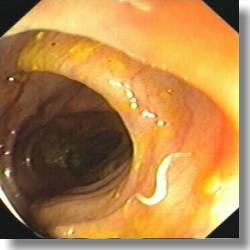

ENTEROBIOSIS

Enterobios vermicularis

Gusanos adultos 1 cm